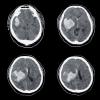

ALO Dokter. Laki-laki 24 tahun dengan kejang fokal berulang dan gangguan kognitif. Hasil CT scan mempelihatkan gambaran berikut:

Apakah sejawat mengenali gambaran khas CT scan tersebut?

Apa kemungkinan diagnosis yang paling mungkin ?

Dan PF khas apakah yang sejawat dapat temui pada kasus ini?

Gambara diatas disebut sebagai tram track sign yaitu kalsifikasi di regio kortikal otak khas pada sindrom Sturge Weber disertai hemicerebral atrophy.

Pada pemeriksaan fisik biasanya kita akan menemukan port wine stain pada area wajah pasien.